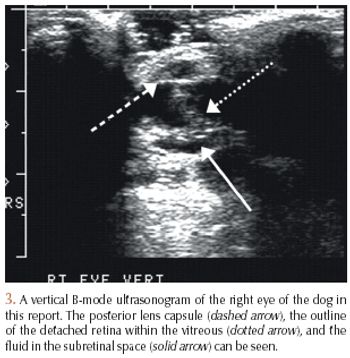

History, ocular surface diagnostics, tonometry, culture and sensitivity, cytology, biopsy, ERG, ultrasound